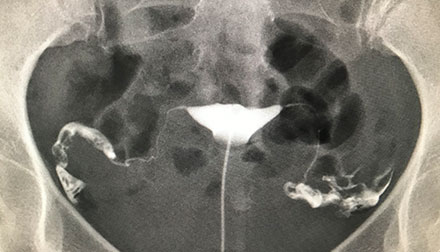

子宮卵管造影検査

造影剤を子宮に注入し、子宮内の異常の有無、卵管が通過しているか、腹腔内に癒着がないか、レントゲンで撮影します。 検査に際しては、痛みを軽減できる装置を使用して実施しています。